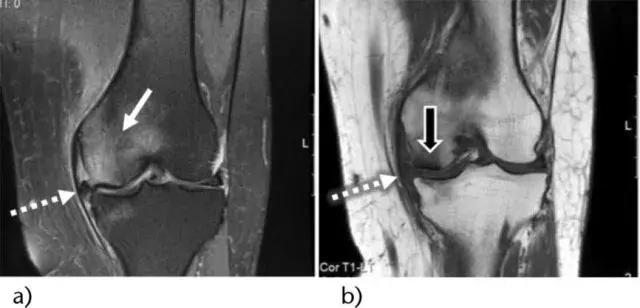

骨髓水肿(bone marrow edema,BME)在临床医生没有充分认识前,常被误诊和漏诊,随着核磁共振成像(MRI)技术的应用普及,诊断准确率得到了有效提高。如果把骨头比作一根木头,那么这根木头外观没有断裂,但里头的木头纤维断裂了,骨髓水肿实际上是构成骨头的骨小梁结构断裂出血,可以理解为微骨折,又称骨挫伤。

如果你的膝痛持续存在,并且并无好转,跑步还使得膝痛不断加重,那么最正确的处理方式就是到医院检查,对于医生来说,往往也无法判断你的膝痛是不是骨髓水肿造成的,但医生会通过询问病情并通过检查进行准确诊断。对于骨髓水肿来说,最有效精准的诊断手段就是核磁共振检查。核磁共振图像显示骨髓异常十分敏感,可以明确骨髓水肿的范围和严重程度。

半月板的损伤和退变在膝痛人群中也极为常见,多见于急性受伤,容易发生在膝关节屈曲同时伴有旋转的动作中。此外,有些人先天半月板发育异常,称为盘状半月板,他们的半月板发育相比正常人大、厚,这样在有限的膝关节空间里,盘状半月板会受到更多的挤压而受伤,如果你常常走路走着走着打软腿,或者关节会突然卡住,又或者关节持续肿胀疼痛,那么一定要到医院进行检查。